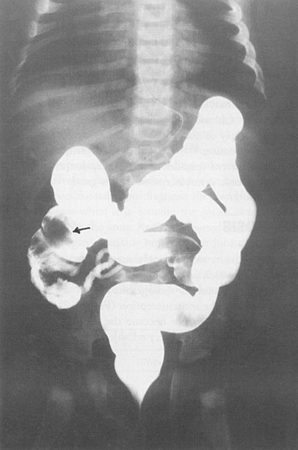

Contrast enema demonstrating ileocolic intussusception (black arrow)

From the collection of Dr KuoJen Tsao; used with permission